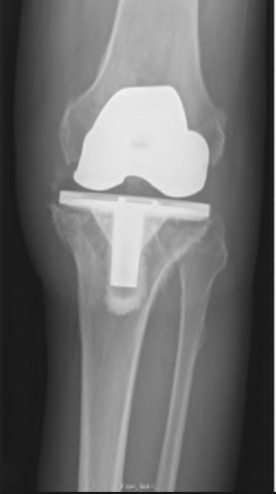

During a revision total knee arthroplasty, removal of the tibial component reveals a massive contained metaphyseal defect measuring 3 cm deep, but with an intact cortical rim. According to the Anderson Orthopaedic Research Institute (AORI) classification, what type of defect is this, and what is the preferred method of management?